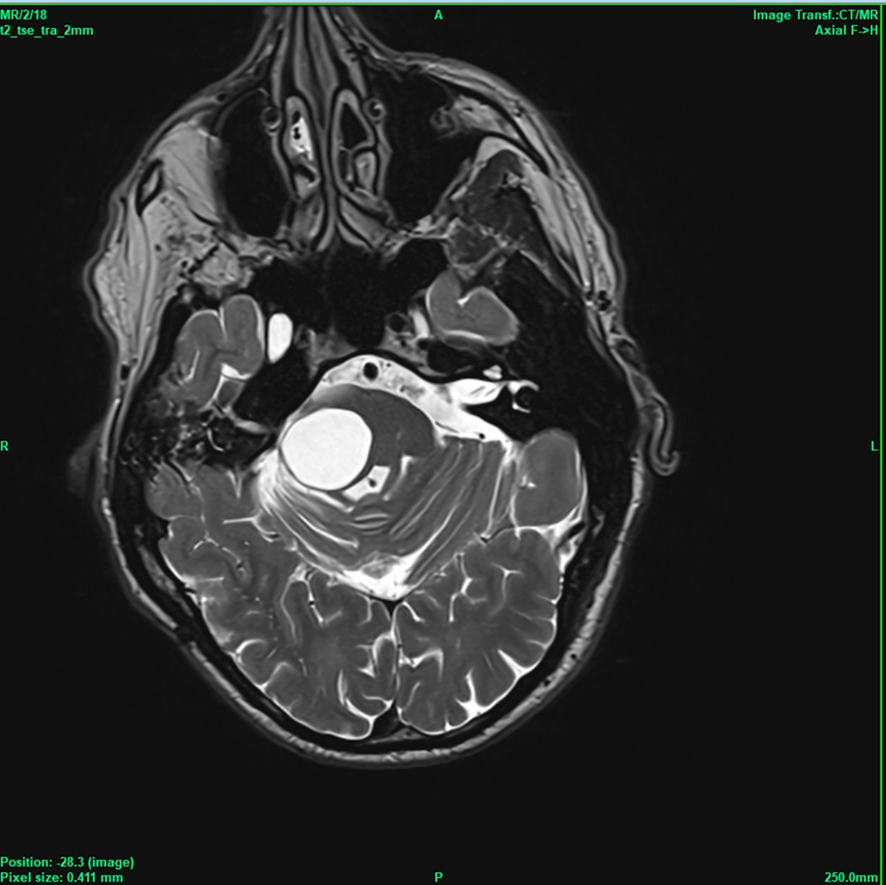

In 2019, gait disturbances reappeared as the cyst enlarged; the Rickham reservoir was found to be occluded and was subsequently removed, followed by stereotactic cyst drainage. In 2023, an open surgical resection and fenestration of multiple cysts were performed. Postoperatively, the patient developed a transient hemiparesis and permanent deafness. In June 2025, the pontine cyst recurred once more, resulting in renewed gait impairment (Figure 1).

Figure 1 Space occupying cyst causing gait disturbances.